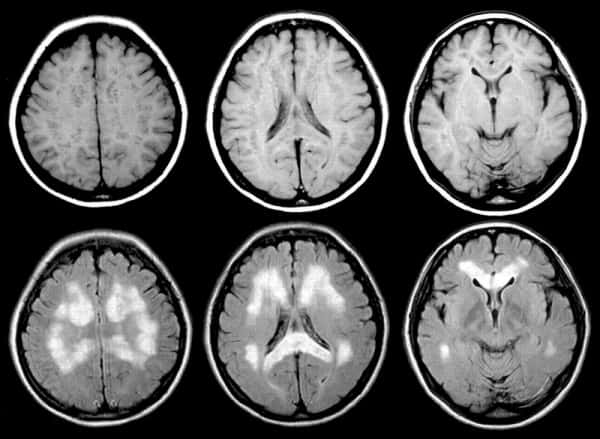

Методы диагностики болезни Паркинсона предполагают сбор анамнеза и клинических данных о начале заболевания. Для визуализации структур головного мозга и определения деятельности клеток используется компьютерная томография, магнитно-резонансная томография (МРТ), позитронно-эмиссионная томография, однофотонная эмиссионная компьютерная томография (ОФЭКТ), метод вызванных потенциалов. Конечно, все эти обследования не используются сразу. Врач подбирает для пациента индивидуальный диагностический комплекс, который позволит выявить болезнь и по возможности найти ее причину.